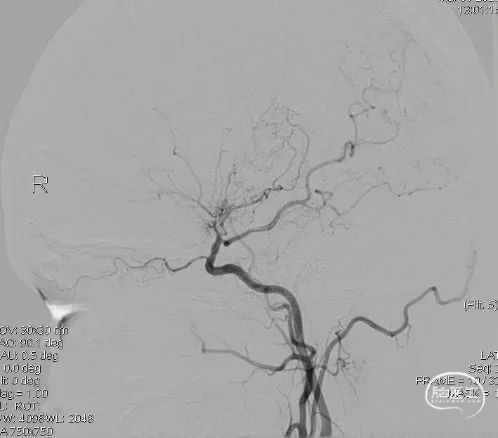

复查DSA:右侧颈外动脉侧位造影显示桥血管(右侧颞浅动脉顶支)走行向大脑半球上外侧面中央前回区域。

周围还可以看到一些颞浅动脉额支和硬膜新生血管供血。